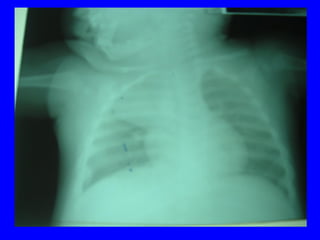

X quang phoåi:  xaùc ñònh , xñònh NN, ñoä naëng

VP thuyø, thaâm nhieãm phoåi, VP moâ keõâ

4.3 Chaån ñoaùn xaùc ñònh:

Laâm saøng: soát+ ho+ thôû nhanh vaø hoaëc co

loõm ngöïc

+ X quang: coù toån thöông phoåi: toån thöông

pheá nang; moâ keõ; toån thöông thuøy phoåi